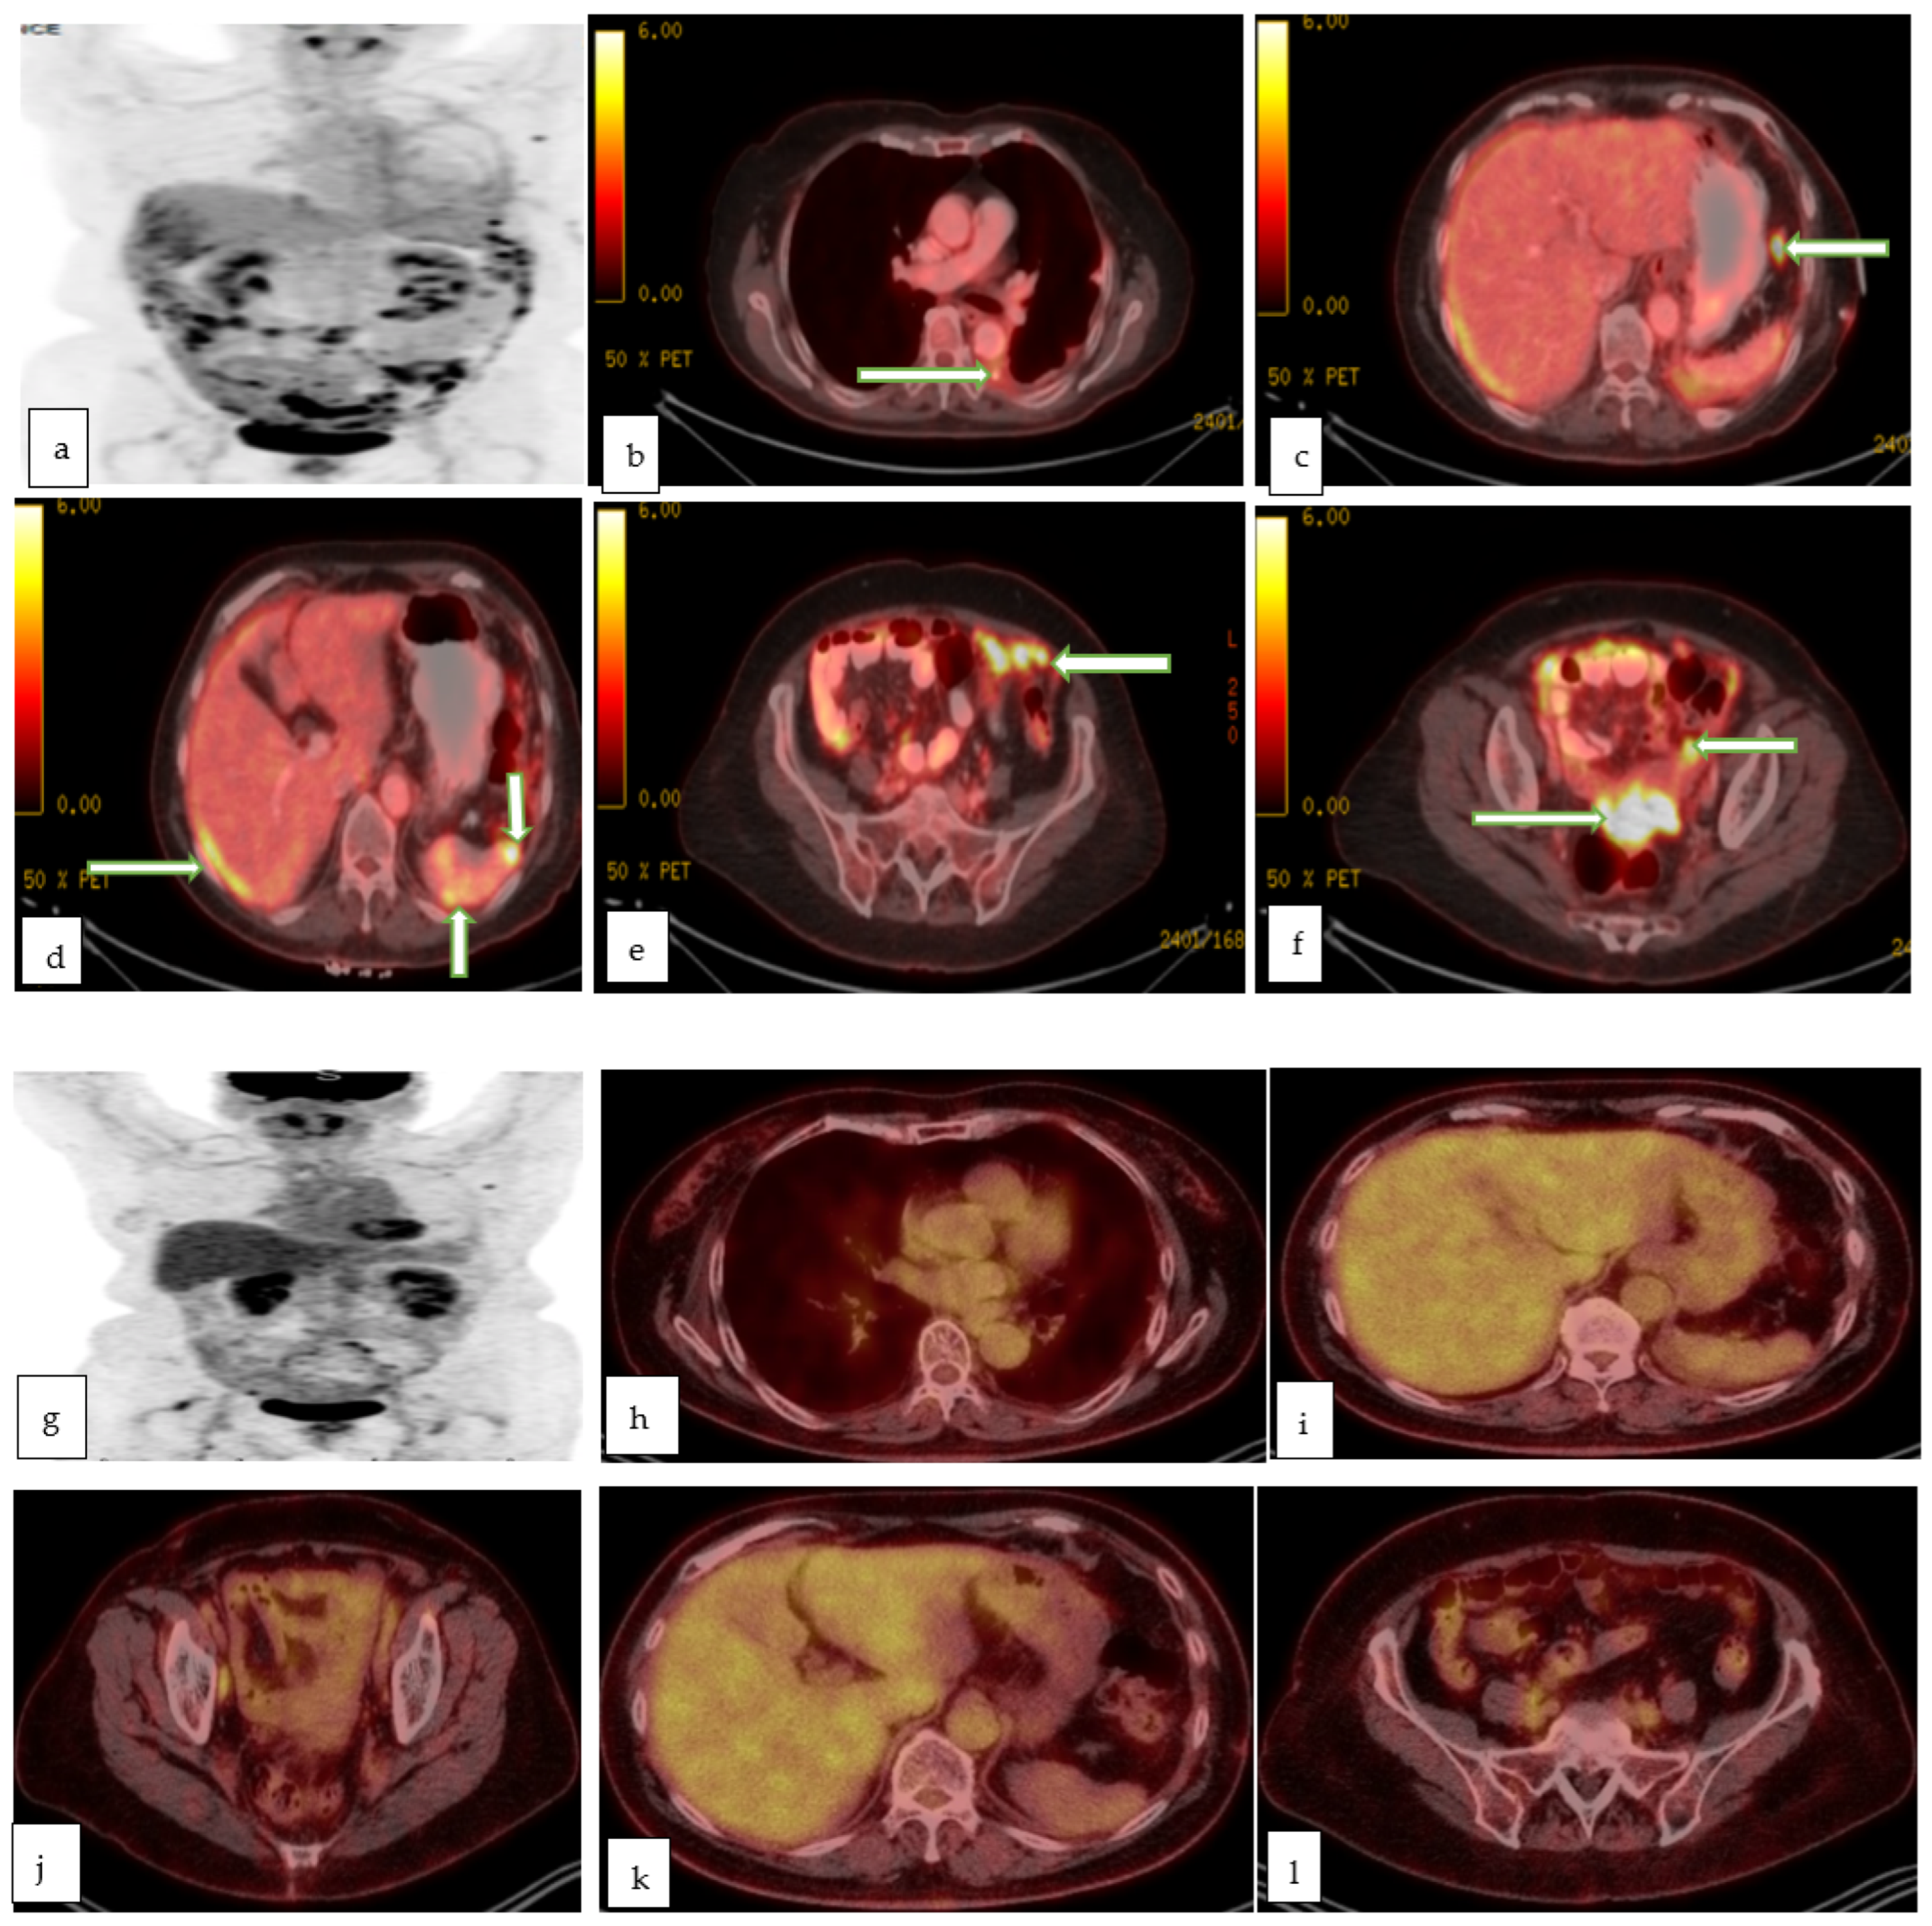

4.4. Molecular Imaging

4.5. Positron Emission Tomography-Computed Tomography (PET-CT)

- Dejanovic, D.; Hansen, N.L.; Loft, A. PET/CT Variants and Pitfalls in Gynecological Cancers. Semin. Nucl. Med. 2021, 51, 593–610. [Google Scholar] [CrossRef] [PubMed]

- Narayanan, P.; Sahdev, A. The role of (18)F-FDG PET CT in common gynaecological malignancies. Br. J. Radiol. 2017, 90, 20170283. [Google Scholar] [CrossRef] [PubMed]

- Kidd, E.A.; Siegel, B.A.; Dehdashti, F.; Grigsby, P.W. The standardized uptake value for F-18 fluorodeoxyglucose is a sensitive predictive biomarker for cervical cancer treatment response and survival. Cancer 2007, 110, 1738–1744. [Google Scholar] [CrossRef] [PubMed]

- Burger, I.A.; Vargas, H.A.; Donati, O.F.; Andikyan, V.; Sala, E.; Gonen, M.; Goldman, D.A.; Chi, D.S.; Schöder, H.; Hricak, H. The value of 18F-FDG PET/CT in recurrent gynecologic malignancies prior to pelvic exenteration. Gynecol. Oncol. 2013, 129, 586–592. [Google Scholar] [CrossRef] [PubMed]

- Fruscio, R.; Sina, F.; Dolci, C.; Signorelli, M.; Crivellaro, C.; Dell’Anna, T.; Cuzzocrea, M.; Guerra, L.; Milani, R.; Messa, C. Preoperative 18F-FDG PET/CT in the management of advanced epithelial ovarian cancer. Gynecol. Oncol. 2013, 131, 689–693. [Google Scholar] [CrossRef]

- Hynninen, J.; Kemppainen, J.; Lavonius, M.; Virtanen, J.; Matomäki, J.; Oksa, S.; Carpén, O.; Grénman, S.; Seppänen, M.; Auranen, A. A prospective comparison of integrated FDG-PET/contrast-enhanced CT and contrast-enhanced CT for pretreatment imaging of advanced epithelial ovarian cancer. Gynecol. Oncol. 2013, 131, 389–394. [Google Scholar] [CrossRef]